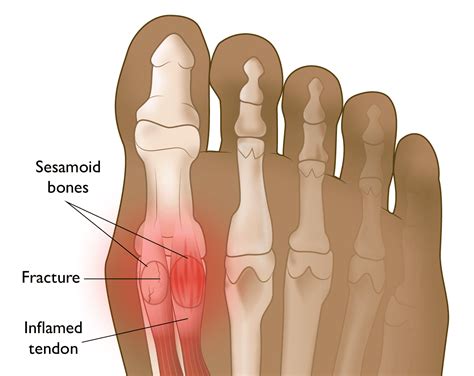

• Sesamoid Fracture: A fracture of the sesamoid bones can occur due to a sudden impact or repetitive stress. This condition is often seen in athletes and dancers.

• Sesamoiditis: This is an inflammation of the sesamoid bones and the surrounding tendons. It is often caused by overuse, high-impact activities, or improper footwear.

• Swelling and tenderness in the affected area